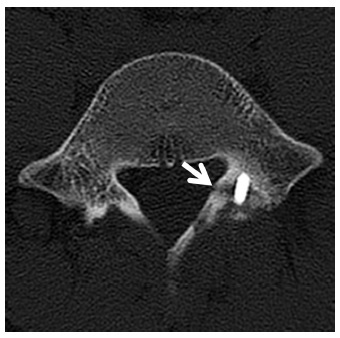

研究共纳入了自 2012 年 6 月至 2013 年 7 月在该部队医院就诊的 1784 例腰痛患者,其中符合研究标准、年龄介于 20 到 30 岁之间的,合计 149 例。根据患者的个人偏好,将 149 例患者分为两组:传统治疗组(包括药物治疗、理疗和注射治疗)和手术组(DR:4.5 mm 皮质骨螺钉固定 植骨)。具体手术技术见图 1。

图 1 腰椎 CT 提示手术技术:右侧峡部以一枚螺钉固定(中图和右图,黑色箭头),左侧峡部以钢丝固定(左图和中图,星号)